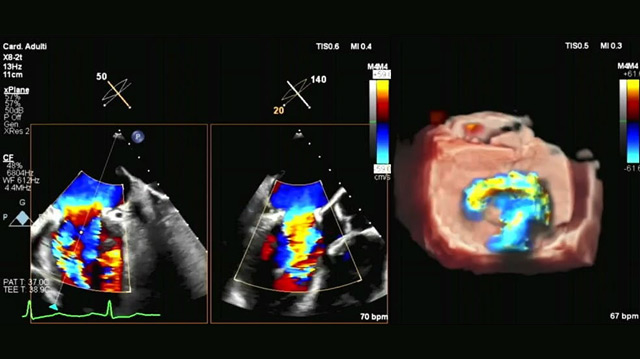

Percutaneous aspiration of vegetation to relieve obstruction in surgically repaired mitral valve

This image highlights the challenges of managing infective endocarditis (IE) and explores the potential role of transcatheter extraction devices in addressing unmet needs for patients who cannot undergo surgery.